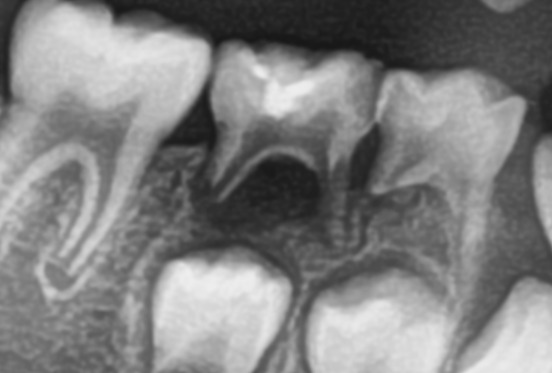

乳牙烂了不及时治,最让人担心的,是直接影响下面的恒牙胚。每一颗乳牙下方,都藏着一颗正在发育的恒牙,就像种子在土里,乳牙是保护种子的土壤。

长期不管的蛀牙,炎症会顺着牙根蔓延到根尖,持续破坏恒牙胚,可能导致恒牙釉质发育不全,新牙长出来自带黄斑、缺损,质地更脆弱,更容易蛀牙。更常见的是,乳牙因为烂得太严重提前脱落,缺牙空隙被两边牙齿挤占,等恒牙萌出时,空间被占,只能歪着长、挤着长,最后一口牙参差不齐,长大后必须矫正,费时费钱又受罪。